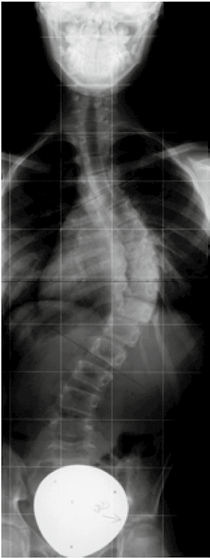

Alle erfolgreichen modernen Weiterentwicklungen der Derotationsorthesen wie z. B. die Korsette nach Rigo System Chêneau (RSC) oder Chêneau light streben eine Spiegelung des Krümmungsmusters und eine Überkorrektur an. Wenn diese Spiegelung nicht erreicht wird, kommt es zu keiner suffizienten Besserung der Skoliose (Abb. 2). Durch Spiegelungskorsette kommt es nicht zur exakten Spiegelung des Cobb-Winkels, sondern nur zu einer Verringerung desselben (Abb. 3). Wichtig erscheint aber nicht nur die Spiegelung, sondern auch die Schaffung ausreichender Freiräume, in die hinein geatmet werden kann und die somit für eine aktive Korrektur sorgen. Insbesondere dorsal ist ein entsprechender Raum wichtig (Abb. 4).

Für die meist jungen Patientinnen steht nicht der gemessene Cobb-Winkel im Vordergrund. Zwar ist dies ein Parameter, an dem sich der Therapieerfolg messen lässt, dennoch erscheinen Symmetrie und kosmetische Aspekte für die Patientinnen wesentlich wichtiger. Das behandelnde Team, bestehend aus Orthopäden, Orthopädie-Technikern und Physiotherapeuten, muss sich also auch hieran messen lassen. Ein kosmetisch gutes Ergebnis (siehe Abb. 3a, b u. 5a, b) entschädigt für eine jahrelange Versorgung mit einem Korsett, die zu einer deutlichen Minderung der Lebensqualität führt 10. Gut derotierende Rumpf-Korsette haben auf eine mehr oder minder weiche Wirbelsäulen-Verkrümmung der noch wachsenden Jugendlichen einen passiven oder aktiven Korrektur-Effekt. Es stellt sich jedoch die Frage, ob neben der meist guten passiven Korrektur in einem modernen derotierenden Rumpf-Korsett auch eine entsprechende aktive Aufrichtung durch die Jugendlichen möglich ist.